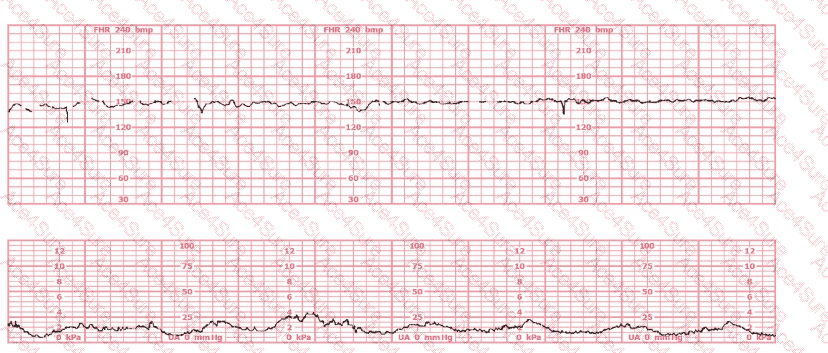

This tracing shows:

Baseline approximately 135–140 bpm

Minimal variability

No accelerations

No recurrent decelerations

Category II for 20 minutes

According to NCC, AWHONN, and NICHD, minimal variability persisting ≥ 20 minutes without accelerations requires assessment of fetal acid-base status, and fetal scalp stimulation is an accepted method to evaluate fetal well-being when a Category II tracing persists.